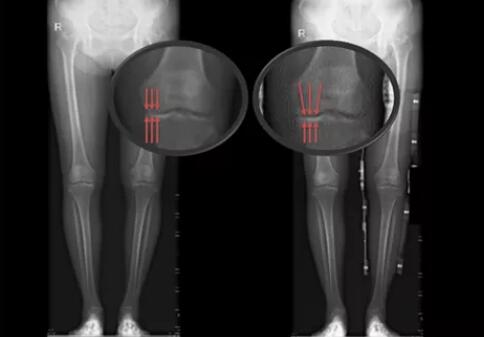

患者未佩戴(左)和佩戴(右)新型矫形支具负重位下肢全长X线片

实验数据结果初步证明,受试者佩戴膝关节内侧减压矫形器后,支撑相后期(膝关节承重的重要周期)膝关节外翻角增大,膝关节内侧力线向外侧转移,膝关节内侧压力降低。对于早、中期的膝骨关节炎患者,佩戴合理设计的膝关节矫形支具能够矫正下肢力线,从而减轻患髁受力,减轻疼痛、改善患处功能并增加膝关节稳定性。